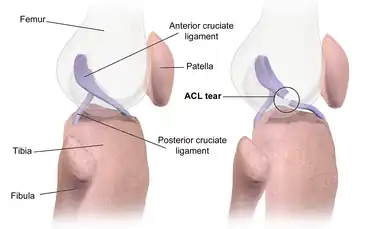

The cruciate ligaments form an "X" inside the knee joint with the anterior cruciate ligament running from the front of the tibia to the back of the femur, and the posterior cruciate ligament running from the back of the tibia to the front of the femur. The anterior cruciate ligament prevents the tibia from sliding out in front of the femur and provides rotational stability.[6]

|

|

| Right knee, front, showing interior ligaments | Left knee, behind, showing interior ligaments |